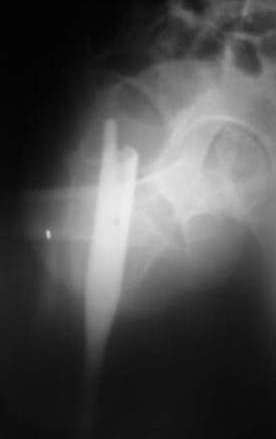

Девушка 21 года 02.10.07 г. пострадала в результате падения с высоты 4-го этажа при пожаре в одном из студенческих общежитий г. Москвы. Получила тяжелую сочетанную травму, в том числе закрытый оскольчатый чрез- и подвертельный перелом левой бедренной кости. Лечилась в одной из больниц столицы. Бедро было фиксировано при помощи скелетного вытяжения. Через полтора месяца после травмы переведена в институт им. Склифосовского. У больной имелись: поддиафрагмальный абсцесс, трахеопищеводный свищ, трахеостома, гастростома, несостоятельность швов раны передней брюшной стенки, укорочение левого бедра на 10 см (рентгенограммы при поступлении - рис 1.). В середине декабря был наложен спицестержневой аппарат, с помощью которого к сегодняшнему удалось устранить укорочение бедра (рис. 2). В течение последних 4-х дней устраняем смещение дистального отломка бедренной кости по ширине. Раны на передней брюшной стенке почти зажили. Температура тела и лабораторные показатели нормальные. Планируем выполнить закрытый остеосинтез левой бедренной кости удлиненным проксимальным бедренным штифтом производства фирмы "Остеомед". Нас смущает, что малый вертел бедренной кости остается значительно смещенным проксимально и кнутри.